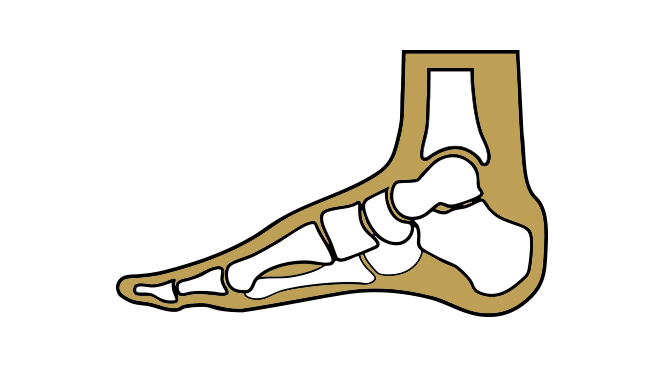

Erkrankungen des Rückfußes

Der Rückfuß bildet die Basis für Stabilität und Bewegung des Fußes und ist besonders belastet bei Gehen und Stehen. In dieser Kategorie erhalten Sie einen Überblick über häufige Erkrankungen des Rückfußes, deren Ursachen, typische Symptome und mögliche Therapiemöglichkeiten.

Viele Menschen mit einem Plattfuß haben keine Beschwerden. Bei anderen können jedoch Schmerzen im Fuß, Knöchel oder Bein auftreten, insbesondere nach längerer Belastung. Auch eine Schwellung im Bereich des Innenknöchels, eine eingeschränkte Beweglichkeit des Fußes und eine schnelle Ermüdung können auftreten.

Ursachen

Die Ursachen können vielfältig sein. Angeborene Fehlbildungen, eine Schwäche des Bindegewebes, Übergewicht, falsches Schuhwerk, Überlastung, Verletzungen oder auch neurologische Erkrankungen können eine Rolle spielen.

Konservative Therapie

Das Tragen von stützenden Einlagen, die das Fußgewölbe anheben, Schuhe mit guter Unterstützung, Fußgymnastik zur Kräftigung der Fußmuskulatur, Gewichtsreduktion und entzündungshemmende Medikamente können die Beschwerden lindern.

Operative Therapie

In seltenen Fällen, wenn die konservativen Maßnahmen nicht ausreichend helfen und die Schmerzen den Alltag erheblich beeinträchtigen, kann eine Operation in Erwägung gezogen werden. Dabei werden je nach Ursache und Ausprägung des Plattfußes verschiedene operative Verfahren eingesetzt, um das Fußgewölbe wiederherzustellen und die Fehlstellung zu korrigieren.